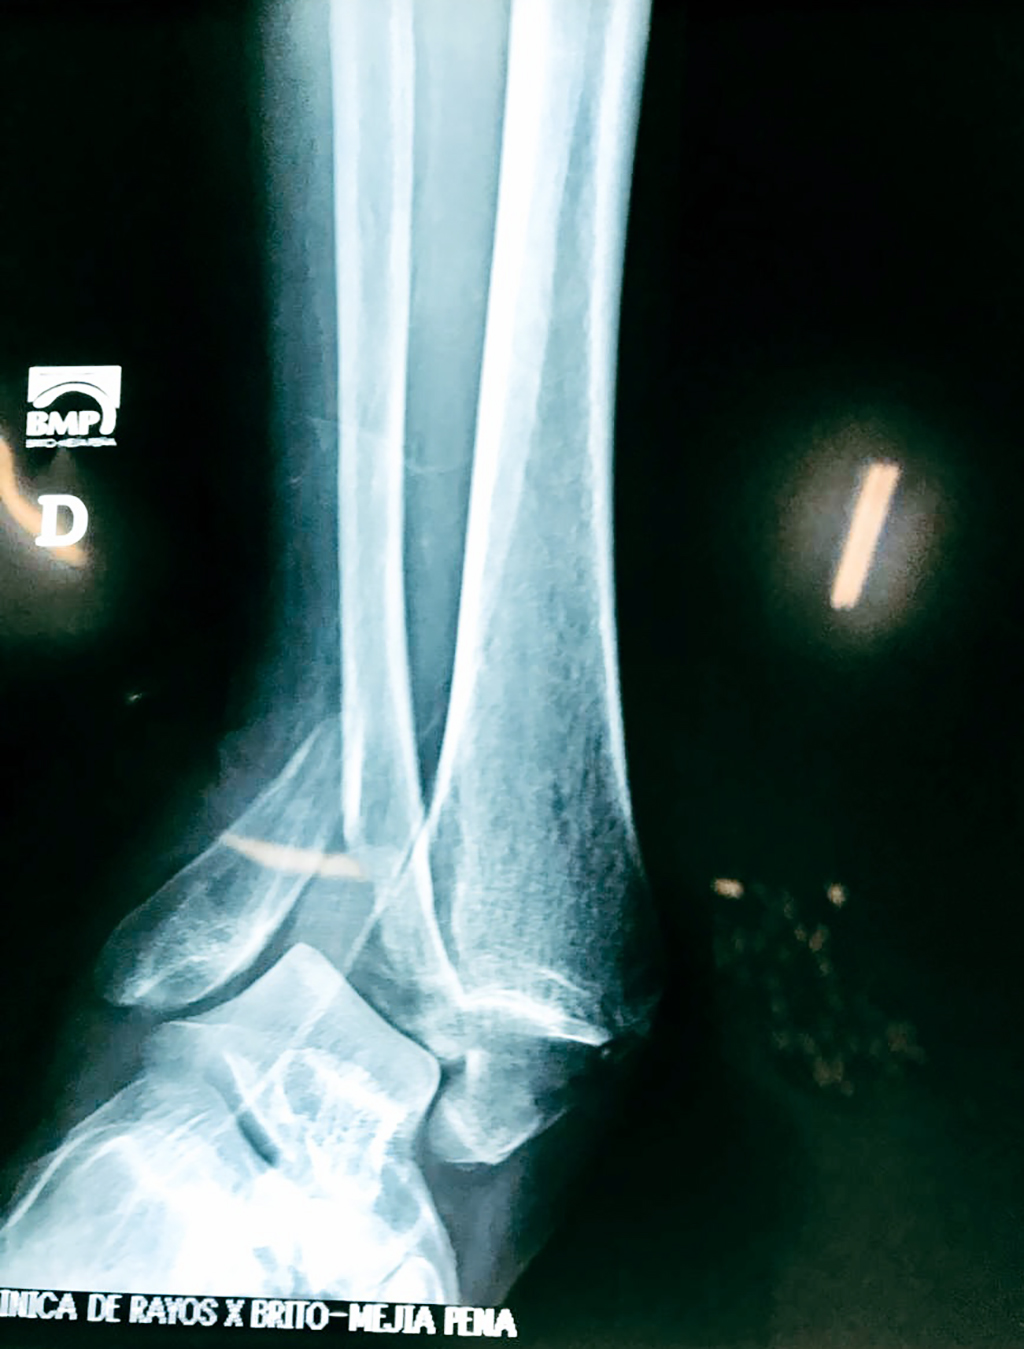

Una fractura de tobillo es la rotura de uno o más de los huesos del tobillo. Estas fracturas pueden ser:

- Producirse en uno o ambos lados del tobillo.

- Los extremos de los huesos están desalineados entre sí (desplazados).

Cuando se necesita cirugía, es probable que esta implique el uso de clavijas de metal, tornillos o placas para sostener los huesos en su lugar mientras la fractura se consolida. Los elementos de soporte pueden ser temporales o permanentes.